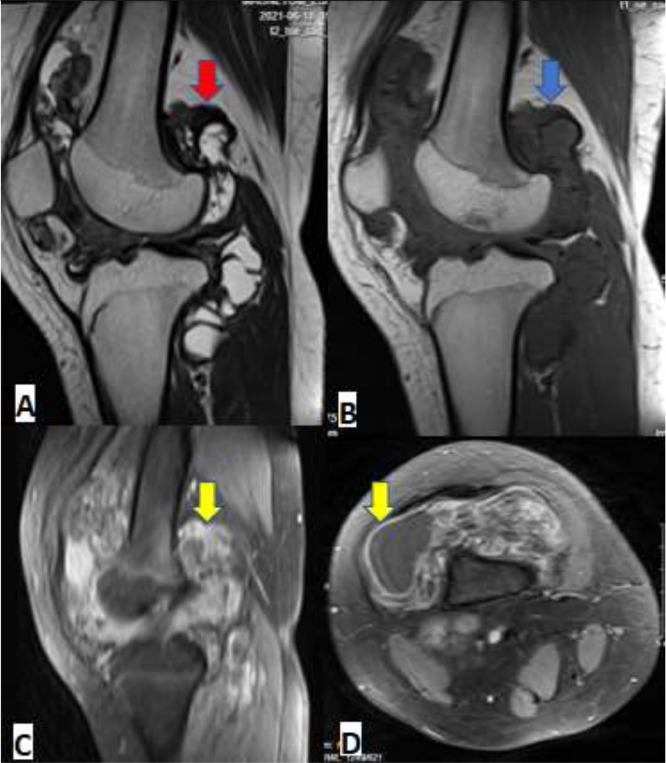

Pigmented villonodular synovitis is a rare proliferative process, especially in children. Pigmented villonodular synovitis can affect the synovial joint, tendon sheaths, and bursa membranes. Within synovial joint involvement, it is commonly seen in the knee joint but hip, ankle, shoulder, wrist, and other joints can be involved. The appearance characteristic is found on a magnetic resonance imaging scan. Complete excision and synovectomy are the usual treatment. In this article, we report a case of pigmented villonodular synovitis of the knee in a 12- year-old girl who underwent total synovectomy after the diagnosis was confirmed by biopsy. Three years after surgery, neither recurrence nor joint degeneration was found. The osteochondral defect at the tibial plateau was filled with calcium phosphate bone paste.

色素沉着绒毛结节性滑膜炎是一种罕见的增殖性病变,在儿童中尤为少见。色素沉着绒毛结节性滑膜炎可累及滑膜关节、腱鞘和滑囊。在滑膜关节受累的情况下,常见于膝关节,但髋关节、踝关节、肩关节、腕关节和其他关节也可受累。其外观特征可通过磁共振成像扫描发现。完整切除和滑膜切除术是常用的治疗方法。在本文中,我们报告了一例12岁女孩膝关节色素沉着绒毛结节性滑膜炎的病例,该女孩在活检确诊后接受了全滑膜切除术。术后三年,未发现复发及关节退变。胫骨平台的骨软骨缺损用磷酸钙骨糊填充。